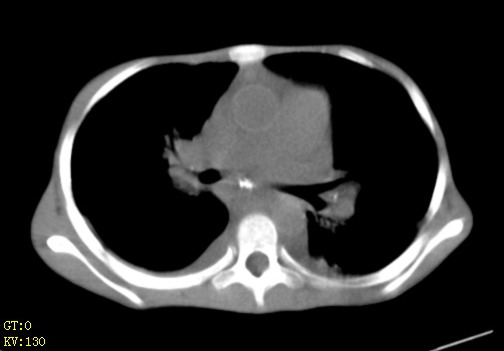

女,12岁,气促、咳嗽2天,3个月前查胸片示:两肺感染,急诊入院查ct,血常规等未检查。

左肺上叶改变考虑继发性肺结核,余双肺重症肺炎不排除h1n1。双侧胸腔少量积液。

双肺中下野不规则片絮状阴影,中外带明显,双侧胸腔少量积液,心影增大,心腔密度减低,隆突下及左侧气管旁见钙化淋巴结影,考虑双肺感染、心衰;建议结合临床除外h1n1并急性心衰,先心不能排除。

两肺多发片絮状模糊影,以下肺外带居多,内见支气管气像,纵膈窗未减影,两侧胸腔积液,心影增大,结合心超,支持重症肺炎,非常时期,甲型h1n1流感不排除。

心衰 双肺霉菌感染,左上肺继发结核。